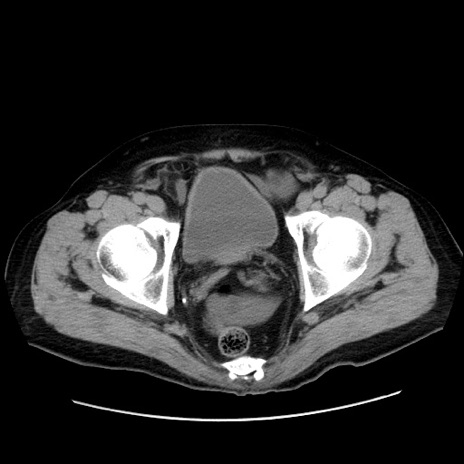

症例30(横断像)

【症例】80歳代男性

【現病歴】約6時間前から臍下部痛が出現。次第に腹部膨隆・背部痛も生じてきたため来院。背部痛の場所は変化しない。

【身体所見】意識清明、BT 36.3℃、BP  131/87mmHg、P 87bpm、SpO2 100%(RA)、臍周囲自発痛・圧痛あり、反跳痛なし、自発痛部位に一致して板状硬あり、腹部膨隆、腸雑音減弱、CVA tenderness両側陰性。